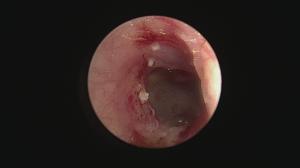

後日、麻酔下でポリープの除去と行いました(今回の処置では、特殊な鉗子を使用し、ポリープを摘出しました)

このように、ポリープを除去すると、耳内の奥も確認できます。

さらに、根元をできるだけ除去し処置終了。

一番奥は中耳内で、鼓膜はすでに消失しています。